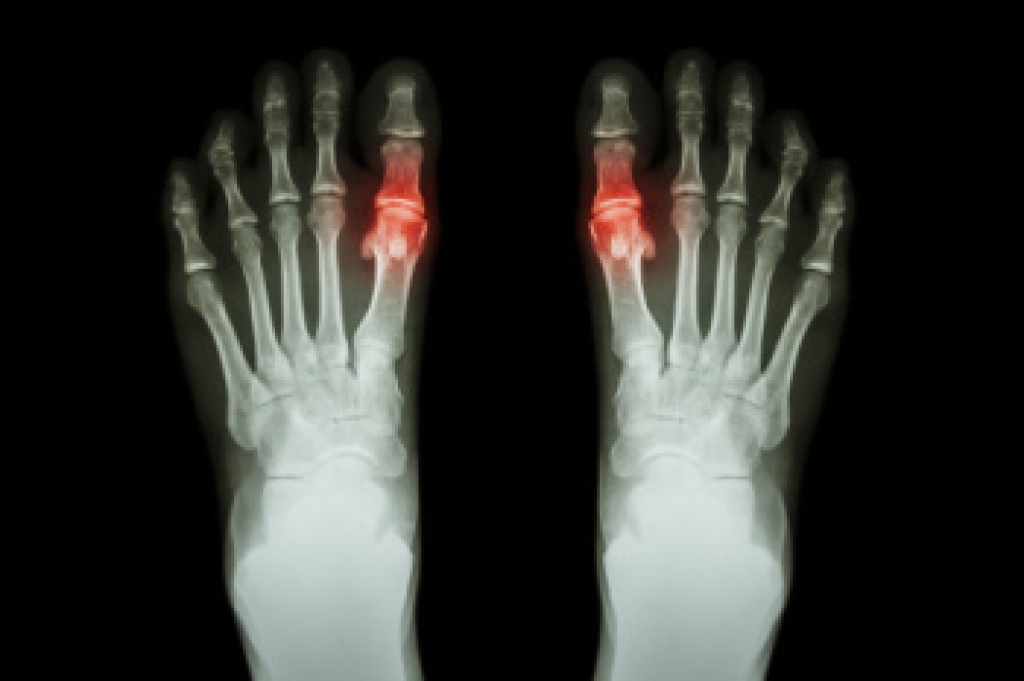

Gout is an inflammatory arthritis caused by the buildup of uric acid crystals within the joints, leading to intense inflammation and discomfort. Symptoms often appear suddenly, and may include swelling, redness, warmth, and severe pain that frequently affects the big toe, but can involve other joints of the foot and ankle. These attacks may occur without warning and can limit walking and daily activity. Causes include elevated uric acid levels in the blood, which may be influenced by diet, genetics, and certain medical conditions. Risk factors include obesity, family history, medications, and metabolic disorders. A podiatrist can diagnose gout through a clinical evaluation, manage painful flare-ups, and develop a treatment plan to protect joint health. If you have symptoms of gout, it is strongly suggested that you are under the care of a podiatrist who can offer you effective relief and management techniques.

Gout is a form of arthritis that is characterized by sudden, severe attacks of pain, redness, and tenderness in the joints. The condition usually affects the joint at the base of the big toe. A gout attack can occur at any random time, such as the middle of the night while you are asleep.

- Intense Joint Pain - Usually around the large joint of your big toe, and it most severe within the first four to twelve hours

- Inflammation and Redness -Affected joints may become swollen, tender, warm and red